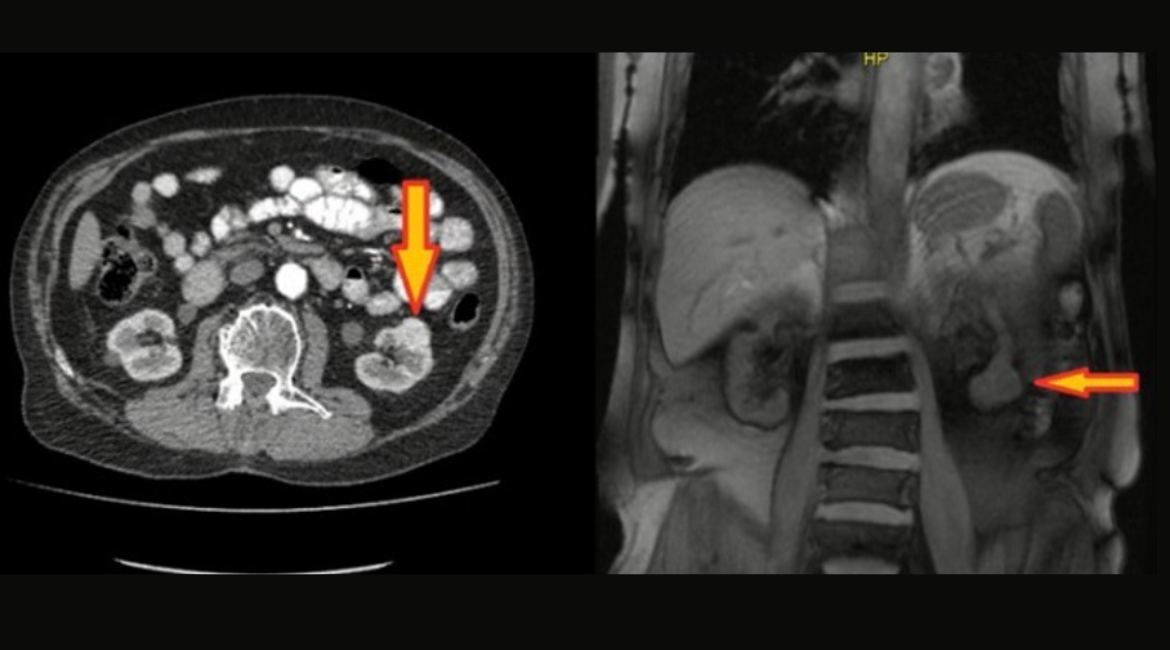

Fumarat hidrataz eksikliği tip renal hücreli karsinom tanılı 64 yaşında erkek hasta.